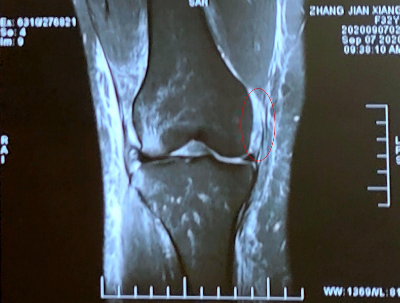

MRI可见:前交叉韧带断裂(红圈所示)